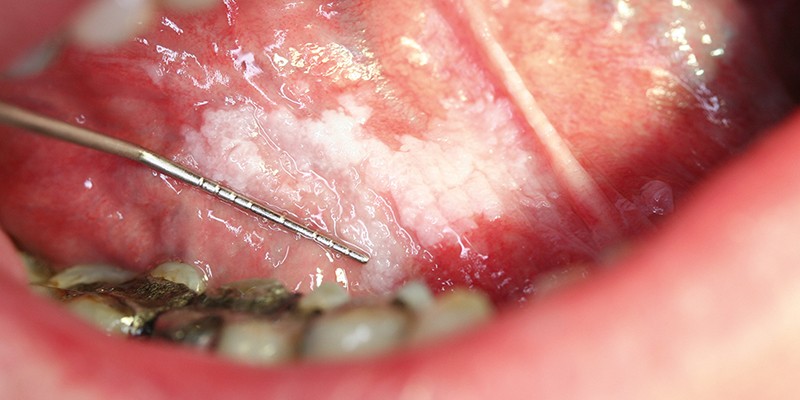

De patiënte bemerkte een witte verkleuring van de tong (leukoplakie) [figuur 1]. Deze premaligne afwijking ontaardt bij 24% van de gevallen in een maligniteit.6 Patiënten met een tongcarcinoom hebben vaak een zwelling of ulcus in de tong [figuur 2]. Aanvankelijk is deze asymptomatisch, maar bij doorgroei ontstaan pijnklachten en mobiliteitsverlies van de tong, waardoor spraak- en slikproblemen kunnen optreden. De pijn kan uitstralen naar de kaak, hals en oren. Bij onderzoek van de tong wijst een geïndureerde zwelling op een maligniteit. Verder let de huisarts op lymfadenopathie van de hals, vooral submandibulair en dorsaal van het kaakkopje. Een biopt van de laesie kan de diagnose bevestigen.